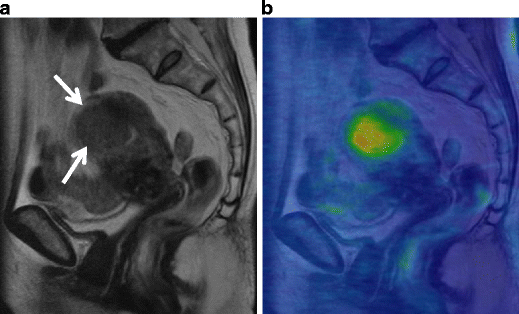

Serous carcinoma in a 55-year-old female. a Sagittal T2-weighted image demonstrates an endometrial tumor of decreased intensity occupying the endometrial cavity, and protruding into the external cervical os. Note the endometrial-myometrial border in both the corpus and cervix is diffusely obscured, suggesting myometrial invasion of the tumor (arrowheads). There is a small implant on the posterior serosal surface of the uterus (arrow). b Fusion image of DWI onto T2-weighted image exhibits increased intensity corresponding to the tumor in the endometrial cavity. The implantation on the posterior wall is also clearly demonstrated with excellent tissue contrast (arrowhead)